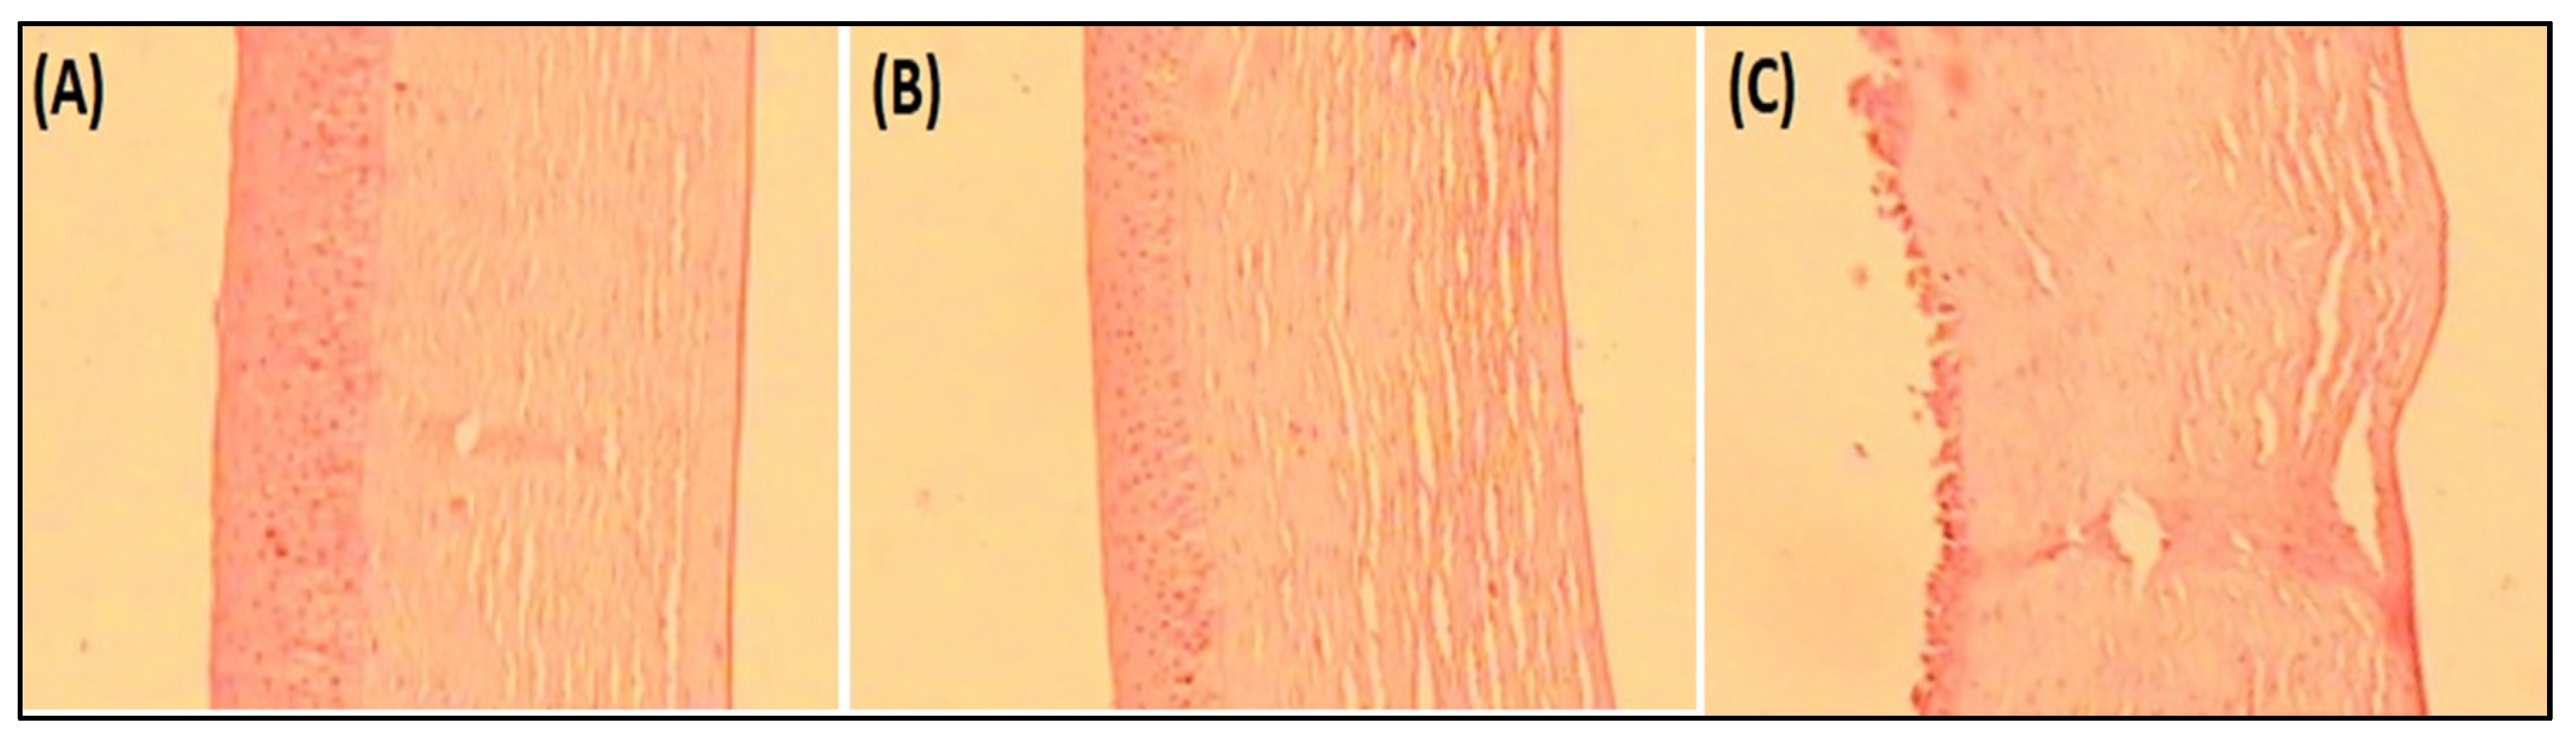

4.8.6. Histopathological Examination

Histopathology study on goat cornea showed the cornea treated with EM-NLCs-opt-IG4 and negative control (0.9% NaCl) had typical corneal structures (Figure 7A,B), and cells retained their normal morphology. It was concluded that, upon treatment, the epidermal layer remains unchanged. The cornea treated with the positive control (1% w/v; SLS) showed damage to the destruction of corneal epithelial cells (Figure 7C). Finally, based on histopathology study, it was established that the EM-NLCs-opt-IG4 was found safe for ocular delivery.

Figure 7.

Histopathological image of (A). EM-NLCs-opt-IG4, (B). Negative control (0.9% NaCl) and (C). Positive control as SLS (1% w/v).